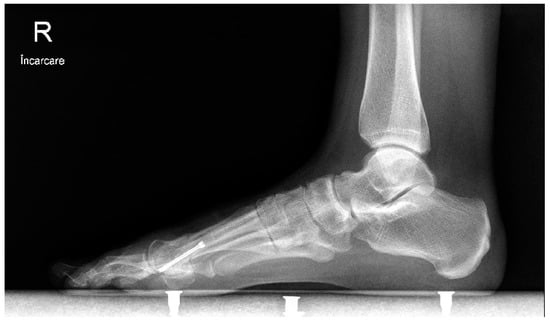

In the open chevron osteotomy group, a 5 cm dorsomedial incision was made. The V-shaped osteotomy was performed using a motor-driven saw. The osteotomy was created in 60 degrees with an angled chevron, and the tip of the osteotomy was positioned 2 mm proximal to the anatomical center of the metatarsal head. The metatarsal head was repositioned in a lateral direction and directly inspected through the incision. The osteotomy was then fixed using a 3.0 mm cannulated screw. The adductor hallucis tendon was released from the fibular sesamoid through a 15 mm dorsal incision. For both groups, the skin was closed using separate 2-0 sutures, and a soft bandage was applied. Postoperative treatment consisted of soft dressings applied weekly. After 3 weeks, the sutures were removed. Full weight-bearing on the forefoot was avoided by wearing an orthosis for six weeks (Figure 3, Figure 4 and Figure 5).

Figure 3. Lateral weight-bearing image at 12 months after surgery.